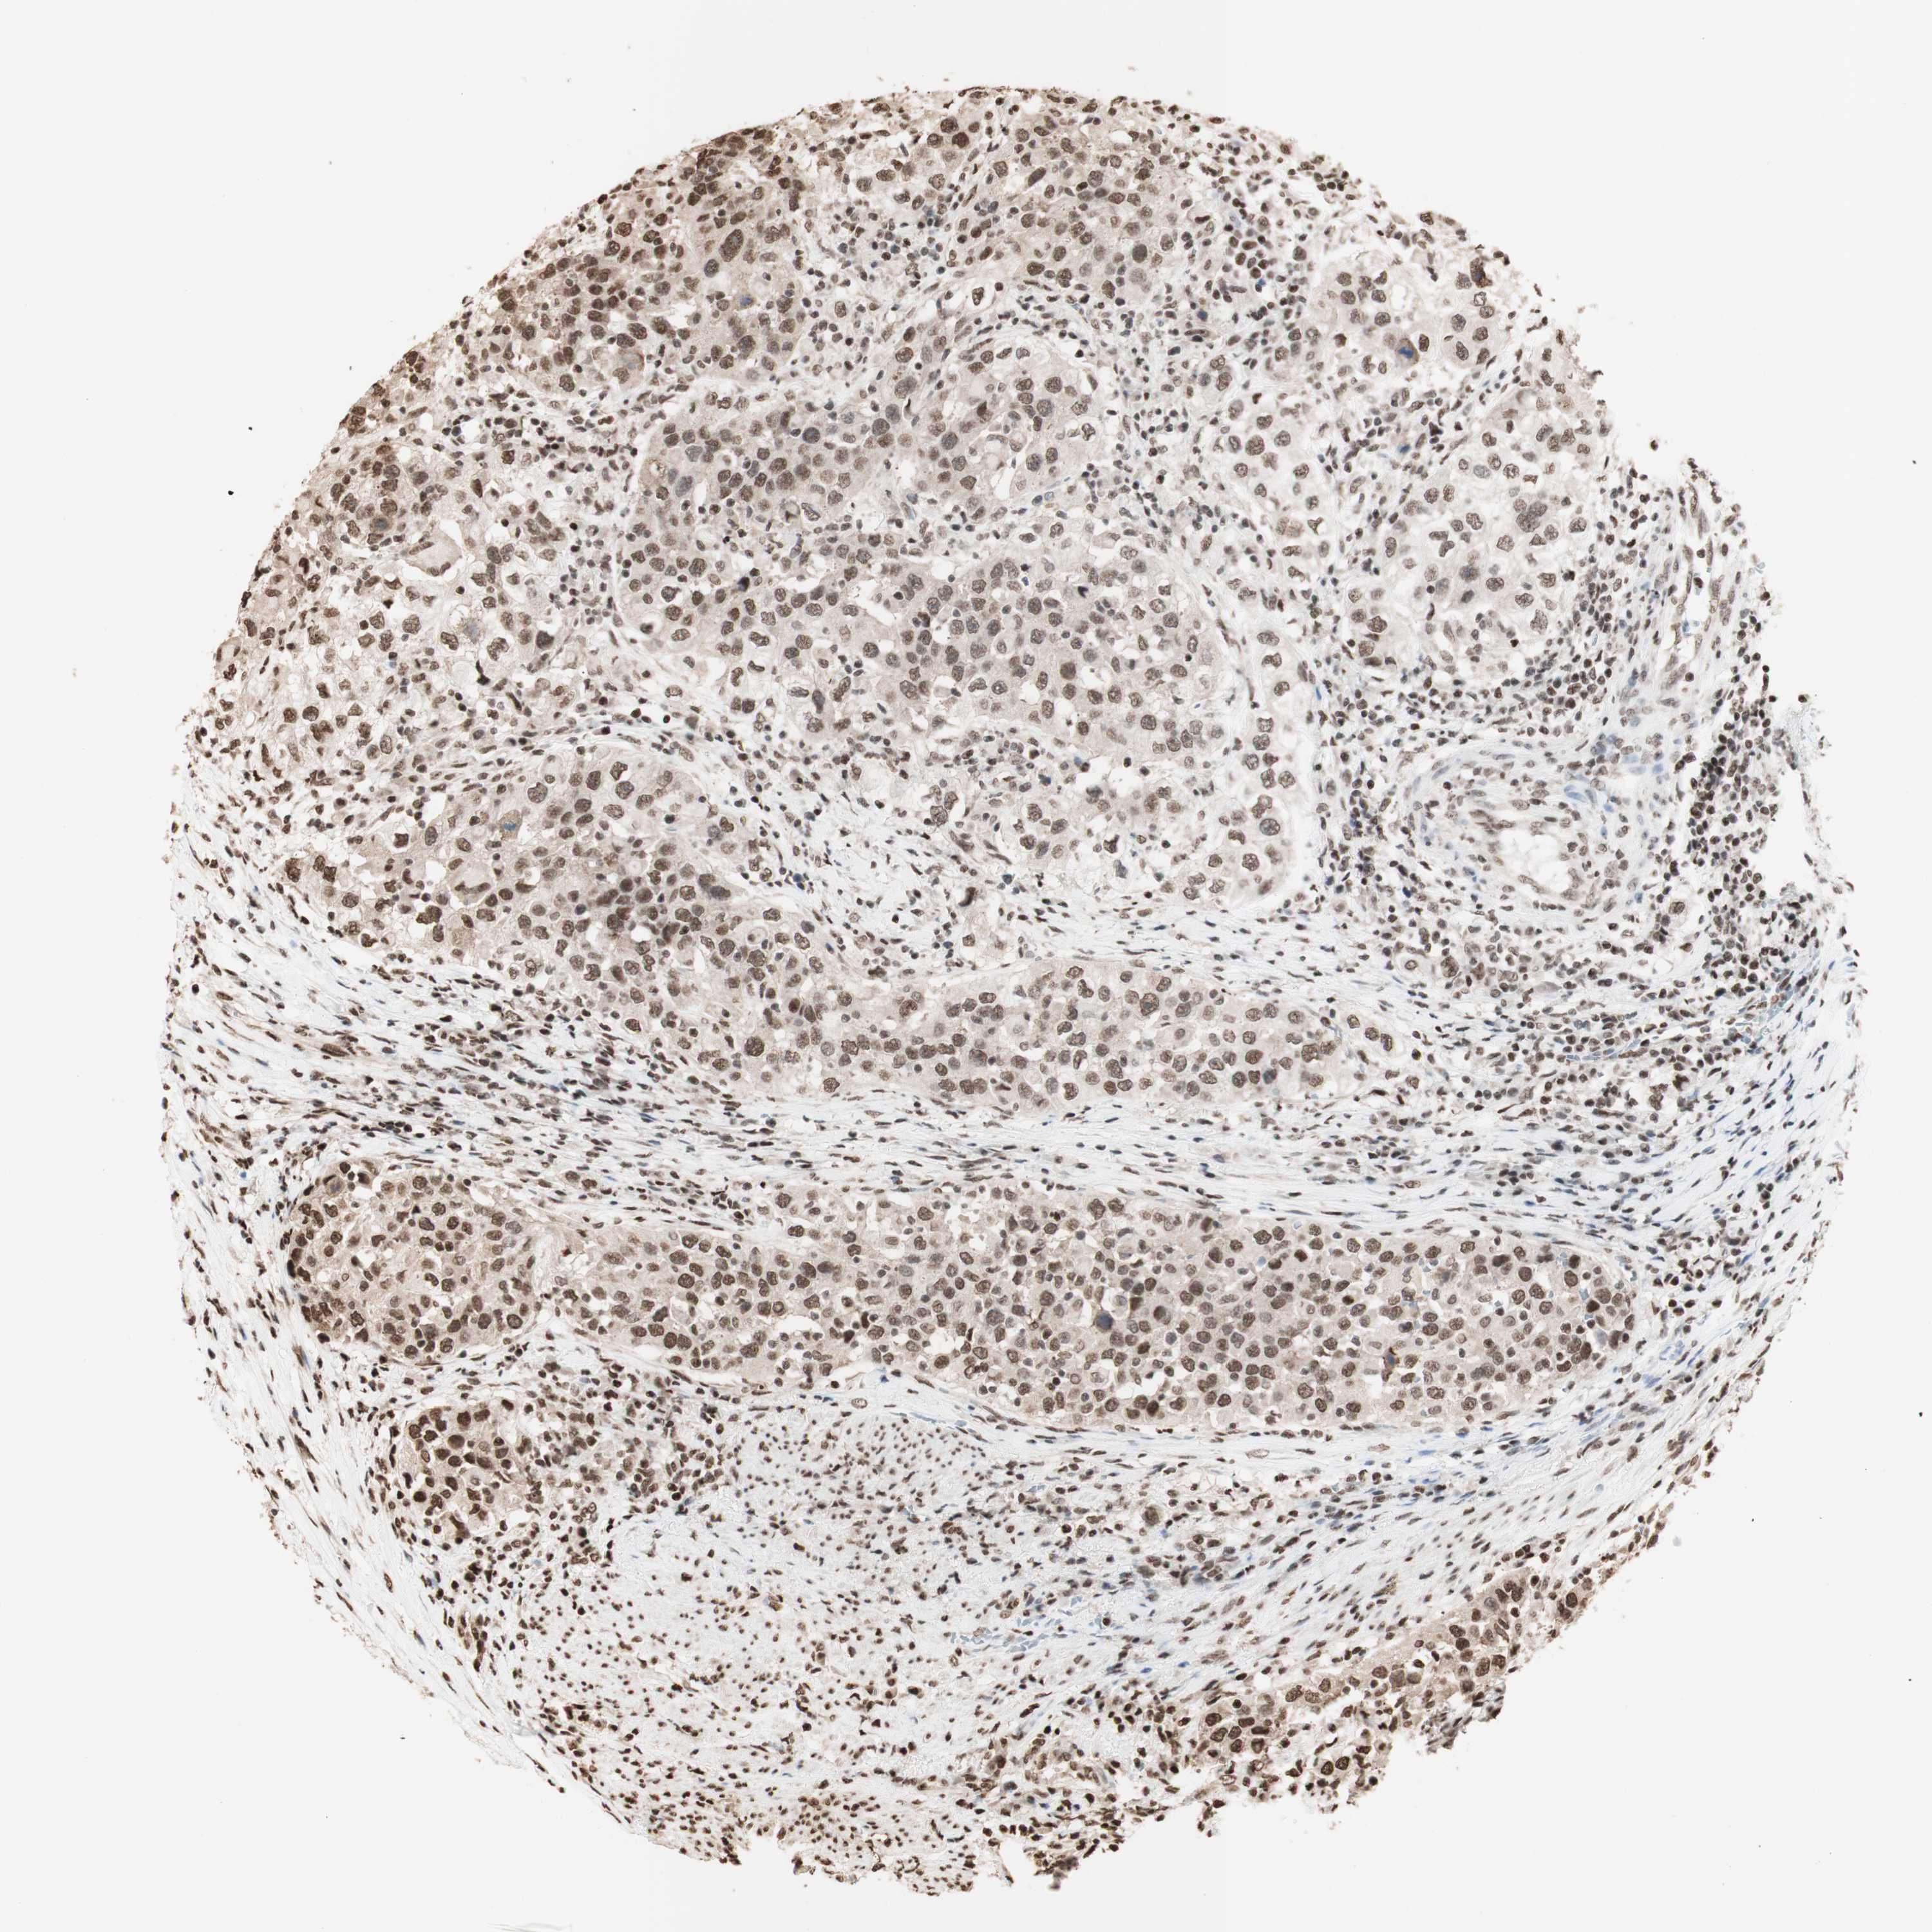

UROTHELIAL CANCER - Protein expressioni

A mouse-over function shows sample information and annotation data. Click on an image to view it in a full screen mode. Samples can be filtered based on level of antibody staining by selecting one or several of the following categories: high, medium, low and not detected. The assay and annotation is described here.

Note that samples used for immunohistochemistry by the Human Protein Atlas do not correspond to samples in the TCGA dataset.

Antibody stainingi

Antibody staining in the annotated cell types in the current human tissue is reported as not detected, low, medium, or high, based on conventional immunohistochemistry profiling in selected tissues. This score is based on the combination of the staining intensity and fraction of stained cells.

Each image is clickable and will lead to virtual microscopy that enables deeper exploration of all samples and also displays staining intensity scores, fraction scores and subcellular localization as well as patient and tissue information for each sample.

Antibody HPA001666

Antibody CAB012403

Staining

High

Medium

Low

Not detected

Intensity

Strong

Moderate

Weak

Negative

Quantity

>75%

75%-25%

<25%

None

Location

Nuclear

Cytoplasmic/membranous

Cytoplasmic/membranous,nuclear

Urothelial carcinoma, High grade

Urothelial carcinoma, Low grade

Adenocarcinoma, NOS